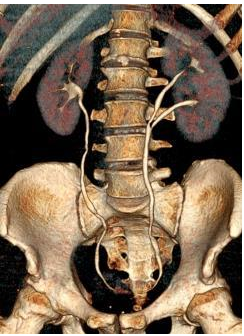

Q

what congenital abnormality has occurred here?

A

horseshoe kidney